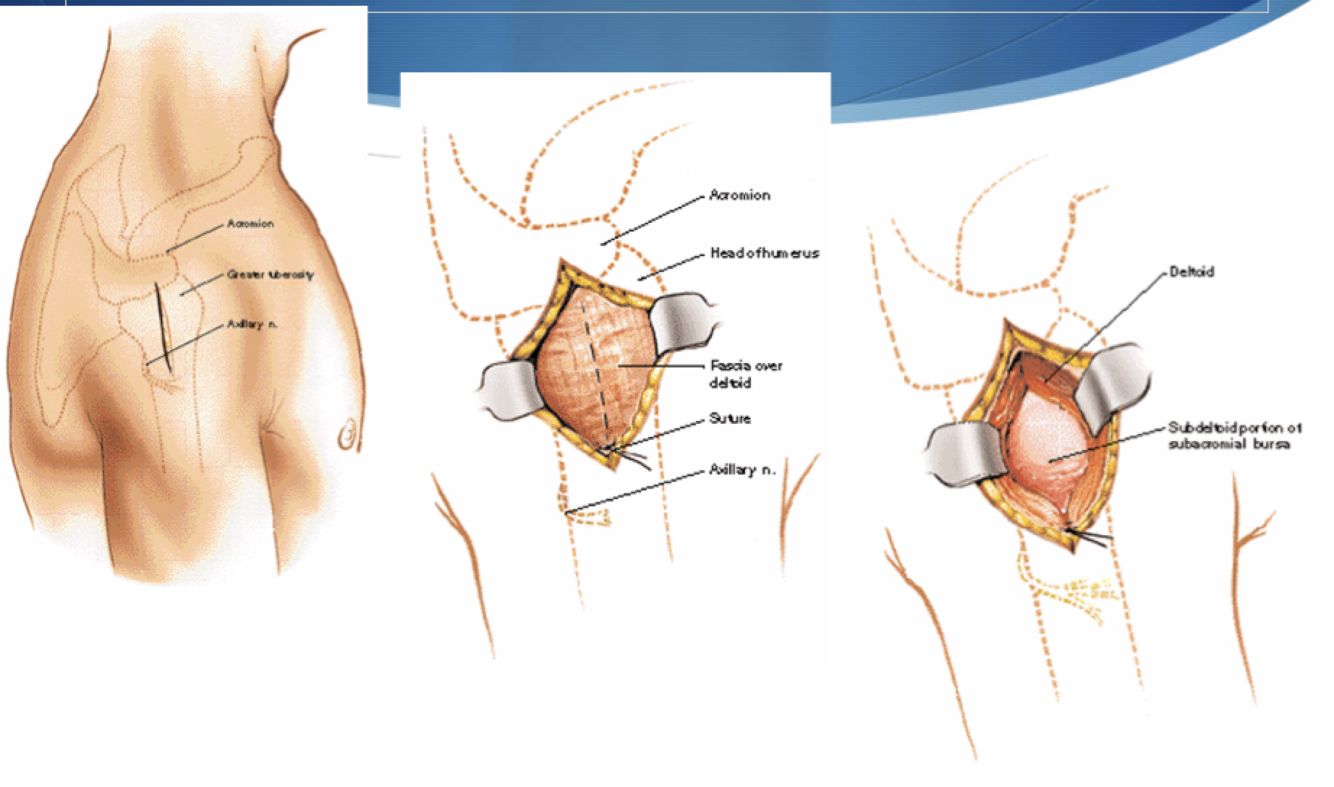

Deltoid Split

Interval: none

Approach: Split fibres of deltoid

Dangers: Axillary n.. Crosses humerus approximately 5-7cm distal from tip of acromion